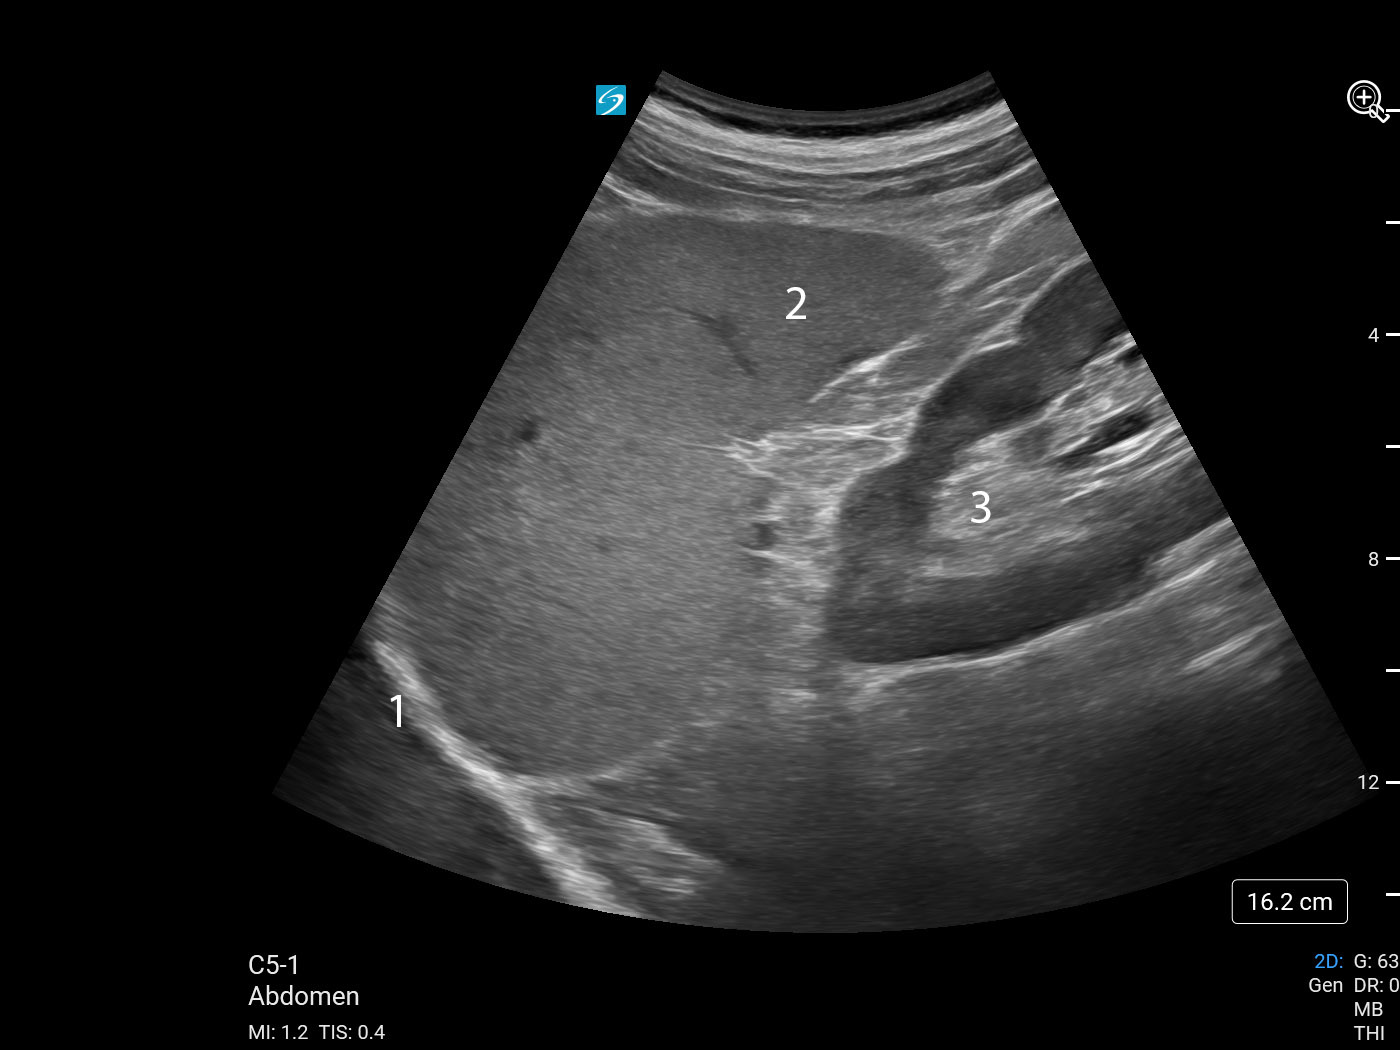

Imagen de cuadrante superior izquierdo (CSI) bazo/riñón izquierdo

1. Diafragma

2. Espacio pleural

3. Bazo

4. Riñón